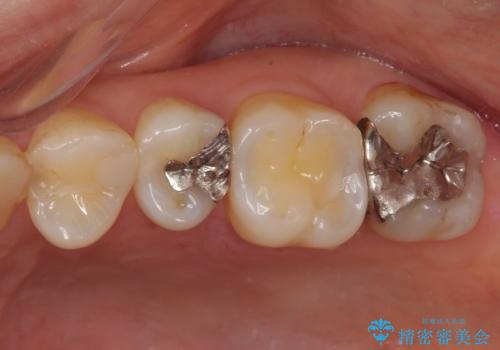

- 奥歯の銀歯をすべてゴールドにすることを希望された患者様です。

セラミックインレーによる補綴治療も提案しましたが、ご自身で強い咬合力を認識しており、歯にもインレーにもダメージの少ないゴールドインレーにて処置することとしました。

ゴールドは「白い歯」ではありませんが、銀歯の金属色とは異なり、非常にきれいな色合いが特徴です。

もちろん、適合が極めて良いという圧倒的メリットもゴールドクラウンやゴールドインレーの特徴です。